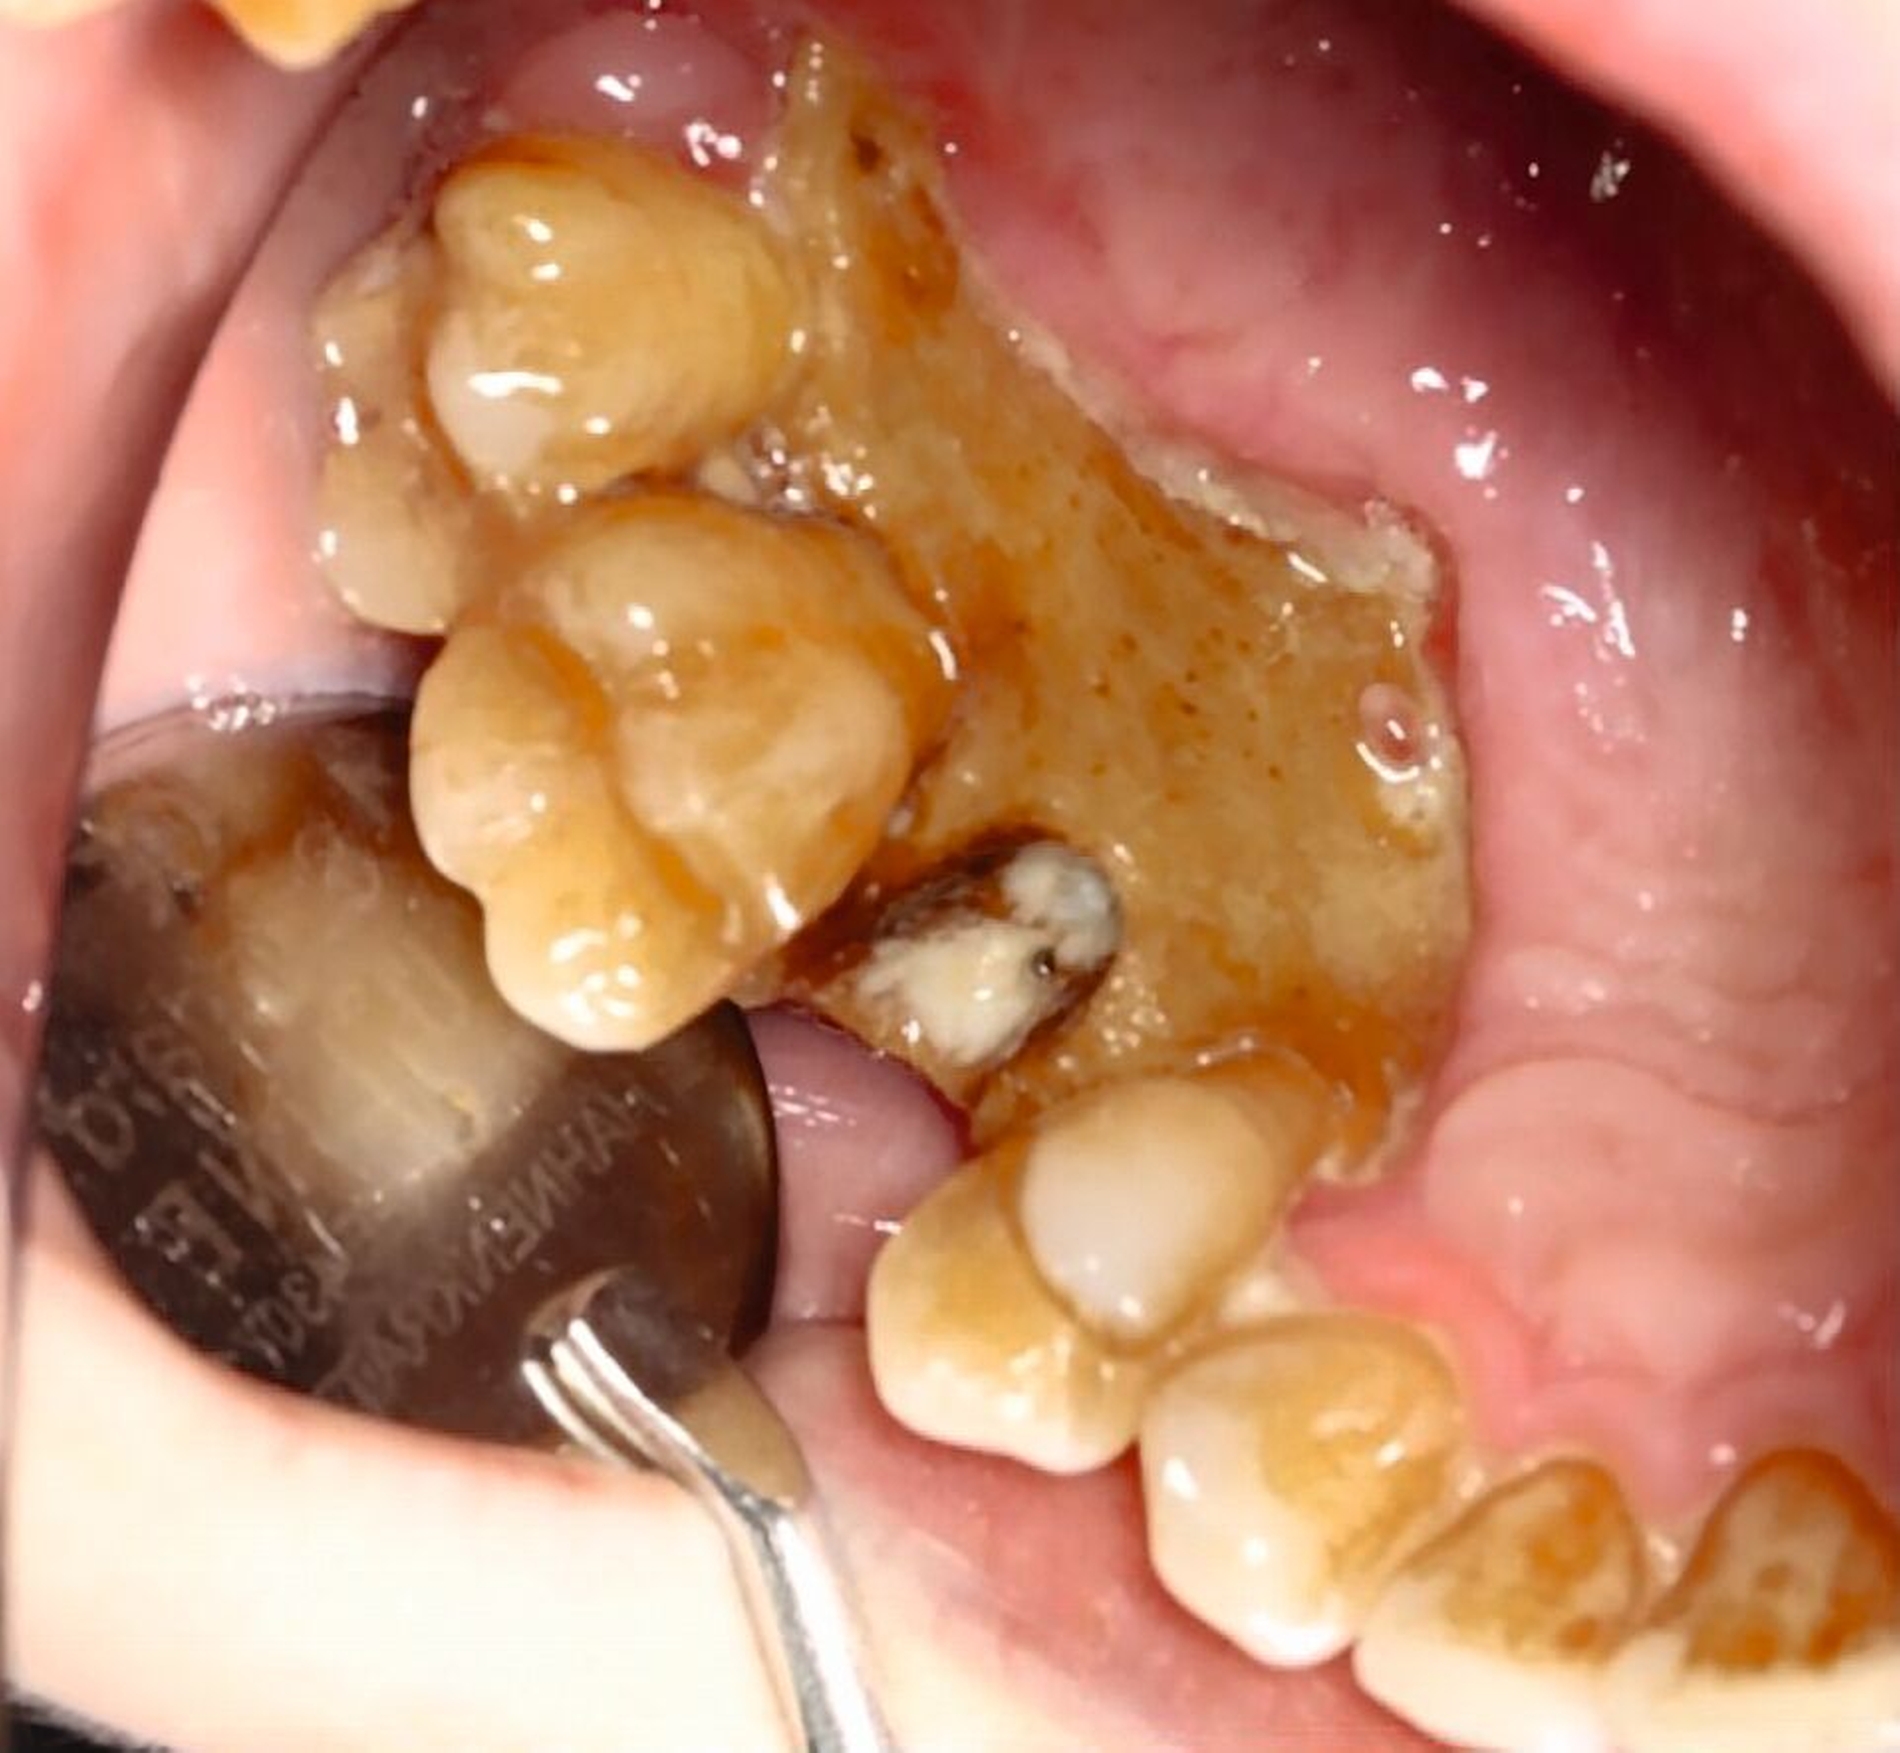

Die klinische Untersuchung zeigte eine ausgeprägte nekroische Schleimhaut palatinal und vestibulär regio 15 bis 17, einen stark gelockerten Zahn 15 sowie einen intensiven Foetor ex ore bei einer auf 2,5 cm eingeschränkten Mundöffnung (Abbildung 1).